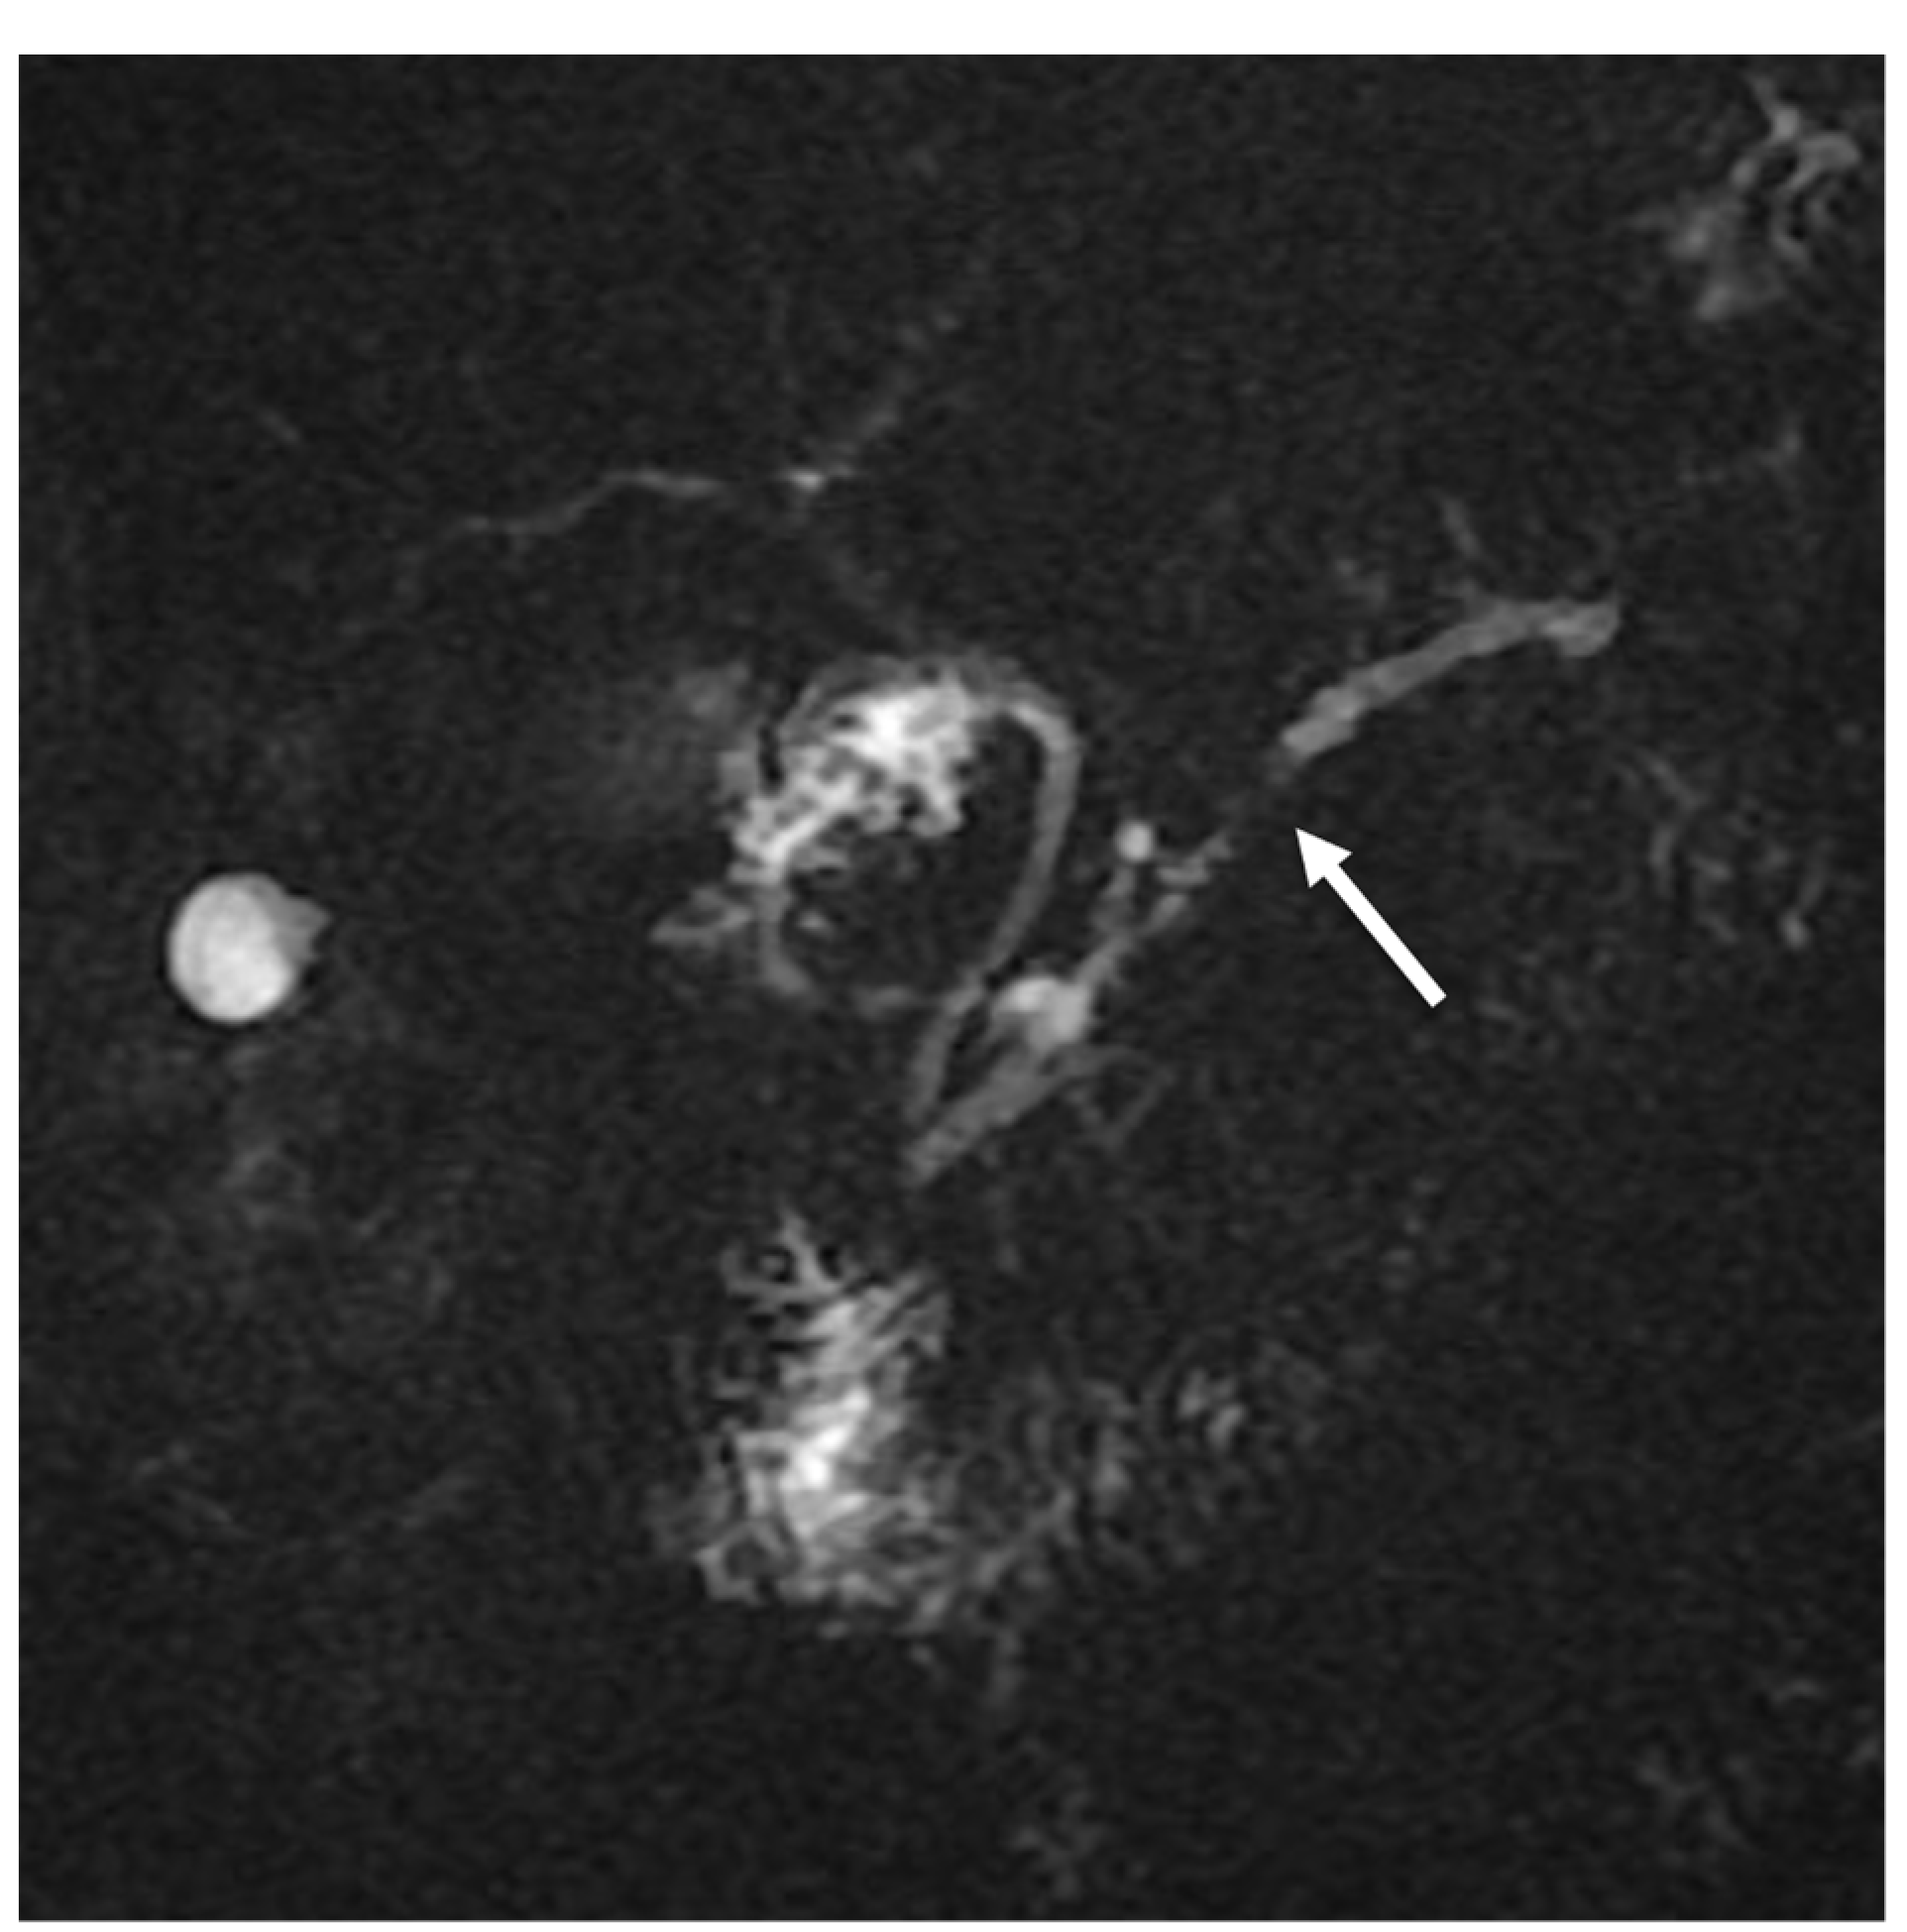

- Fattahi, R.; Balci, N.C.; Perman, W.H.; Hsueh, E.C.; Alkaade, S.; Havlioglu, N.; Burton, F.R. Pancreatic diffusion-weighted imaging (DWI): Comparison between mass-forming focal pancreatitis (FP), pancreatic cancer (PC), and normal pancreas. J. Magn. Reson. Imaging 2009, 29, 350–356. [Google Scholar] [CrossRef] [PubMed]

- Lee, E.S.; Lee, J.M. Imaging diagnosis of pancreatic cancer: A state-of-the-art review. World J. Gastroenterol. 2014, 20, 7864–7877. [Google Scholar] [CrossRef] [PubMed]

- De Robertis, R.; Martini, P.T.; Demozzi, E.; Corso, F.D.; Bassi, C.; Pederzoli, P.; D’Onofrio, M. Diffusion-weighted imaging of pancreatic cancer. World J. Radiol. 2015, 7, 319–328. [Google Scholar] [CrossRef] [PubMed]

- Lee, S.S.; Byun, J.H.; Park, B.J.; Park, S.H.; Kim, N.; Park, B.; Kim, J.K.; Lee, M.-G. Quantitative analysis of diffusion-weighted magnetic resonance imaging of the pancreas: Usefulness in characterizing solid pancreatic masses. J. Magn. Reson. Imaging 2008, 28, 928–936. [Google Scholar] [CrossRef] [PubMed]

- Choi, S.-Y.; Kim, S.H.; Kang, T.W.; Song, K.D.; Park, H.J.; Choi, Y.-H. Differentiating mass-forming autoimmune pancreatitis from pancreatic ductal adenocarcinoma on the basis of contrast-enhanced MRI and DWI findings. Am. J. Roentgenol. 2016, 206, 291–300. [Google Scholar] [CrossRef] [PubMed]